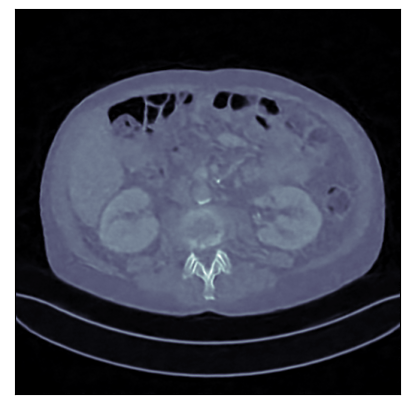

Figure 2: Reconstructed images obtained using different methods, along with the associated PSNR and SSIM, for sparse view CT. In this case the AWCR and AWCR-PD achieve the highest PSNR and SSIM. Furthermore, both AWCR methods retain the fine-structure in the reconstruction, unlike the ACNCR and ACR, the only other methods which possess convergence guarantees.

6.2 Computed Tomography (CT)

For evaluation of the proposed methodology, we consider two applications: CT reconstruction with (i) sparse-view and (ii) limited-angle projection. Supervised methods require access to large high-quality datasets for training, but outside of curated datasets, obtaining large amounts of high-quality paired data is unrealistic. For this reason weakly supervised methods are of significant interest for this problem.

We consider two versions of the AWCR method, one using the subgradient method to solve Equation 1.2 and one using PDHGM, denoted AWCR-PD. These are compared with:

• two standard knowledge-driven techniques: filtered back-projection (FBP) and total variation (TV) regularisation, which act as the baseline;

• two supervised data-driven methods: the learned primal-dual (LPD) method [Adler and Öktem, 2018] and U-Net-based post-processing of FBP [Jin et al., 2017], considered to be state of the art methods in end-to-end learned reconstruction from the two main paradigms: algorithm unrolling and learned post-processing;

• three weakly supervised methods: the AR, ACR, and the ACNCR. Adversarial regularisation methods were chosen as the currently best performing, to the authors’ knowledge, weakly supervised methods for CT.

These comparisons illustrate the trade-offs in levels of constraints and supervision versus stability and performance. For details of the experimental set-up, see Section G.1. We measure the performance in terms of the peak signal-to-noise ratio (PSNR) and the structural similarity index (SSIM) [Wang et al., 2004]. We report average test dataset results in Table 1, with further visual examples in Figure 2.

Sparse view CT As in [Lunz et al., 2018] performance of AR during reconstruction begins to deteriorate if the network is over-trained, so early stopping must be employed in training. For the ACR, ACNCR, and both AWCR methods this does not occur due to reduced expressivity, yet both AWCR methods surpass the performace of AR. Indeed, the AWCR-PD method approaches the PSNR accuracy of the strongly supervised U-Net post-processing method.

Limited view CT In this setting a specific angular region contains no measurement, turning this into a severely ill-posed inverse problem, and a good image prior is crucial for reconstruction. As shown in [Mukherjee et al., 2021], the AR begins introducing artifacts during reconstruction, which is overcome for both the ACNCR and ACR due to the imposed convexity. The AWCR, on the other hand, is able to remain non-convex without experiencing deterioration. However, the AWCR-PD method performs worse in this setting, though still outperforming AR. This occurs due to the forward and the adjoint operator being severely ill-posed. For a visual comparison of the AWCR and AWCR-PD methods in this setting, see Section G.2.